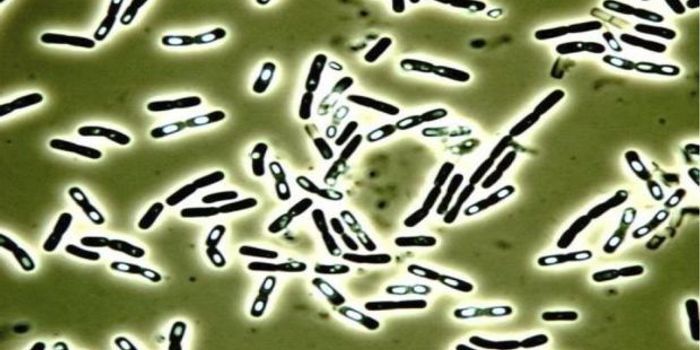

FEB 27, 2015Health & MedicineClostridium difficile (C. difficile, or C. diff) caused almost half a million infections among patients in the United St ...

FEB 27, 2015Health & MedicineATLANTA -- A nasty intestinal bug sickens nearly twice as many Americans each year as was previously thought, according ...

SEP 25, 2015MicrobiologyClostridium difficile is a Gram positive, rod-shaped bacterium commonly found in the soil. However, a small number ...